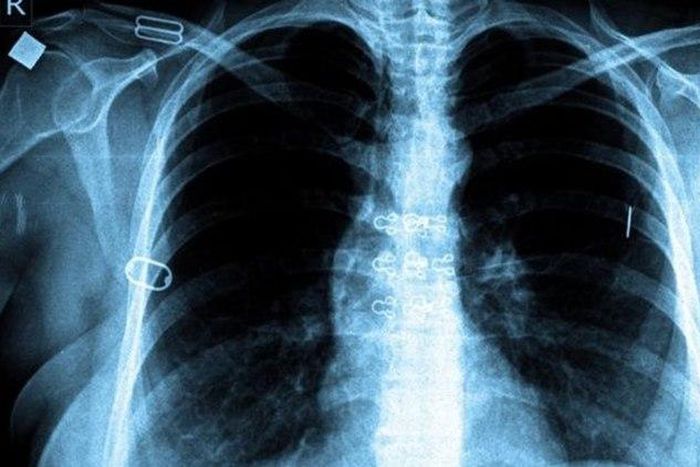

Fight against Tuberculosis paying off globally, report says

The World Health Organisation (WHO)has said that the fight against tuberculosis (TB) is paying off, with this year’s death rate nearly half of what it was in 1990.